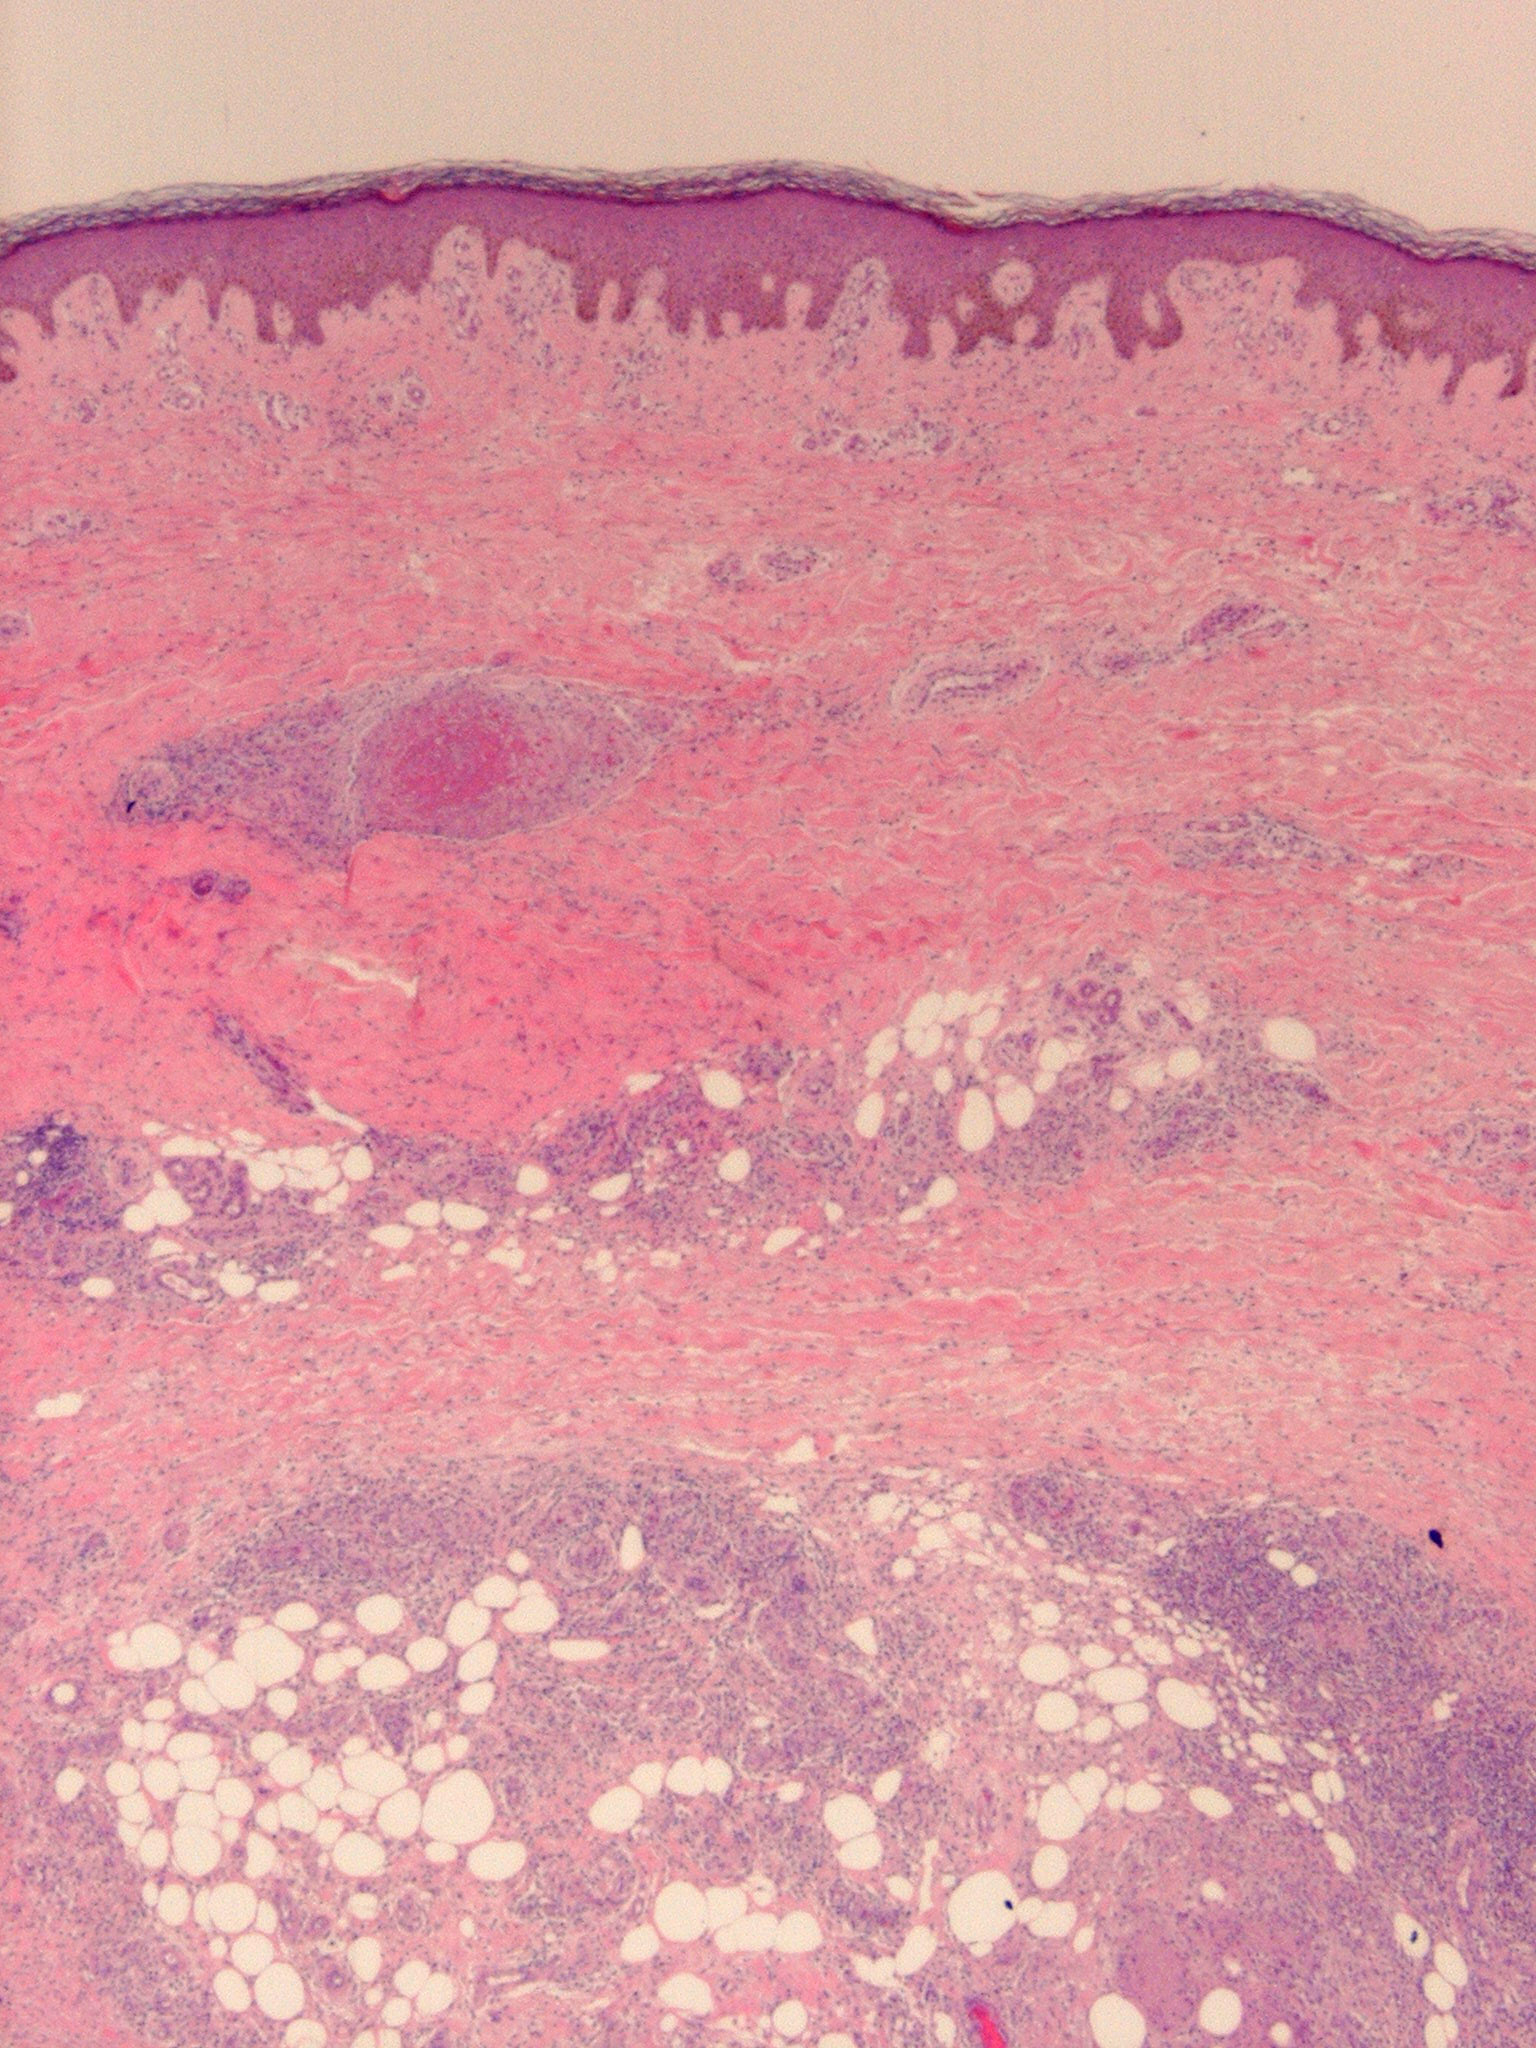

Nodular vasculitis = التهاب الاوعية العقيدي